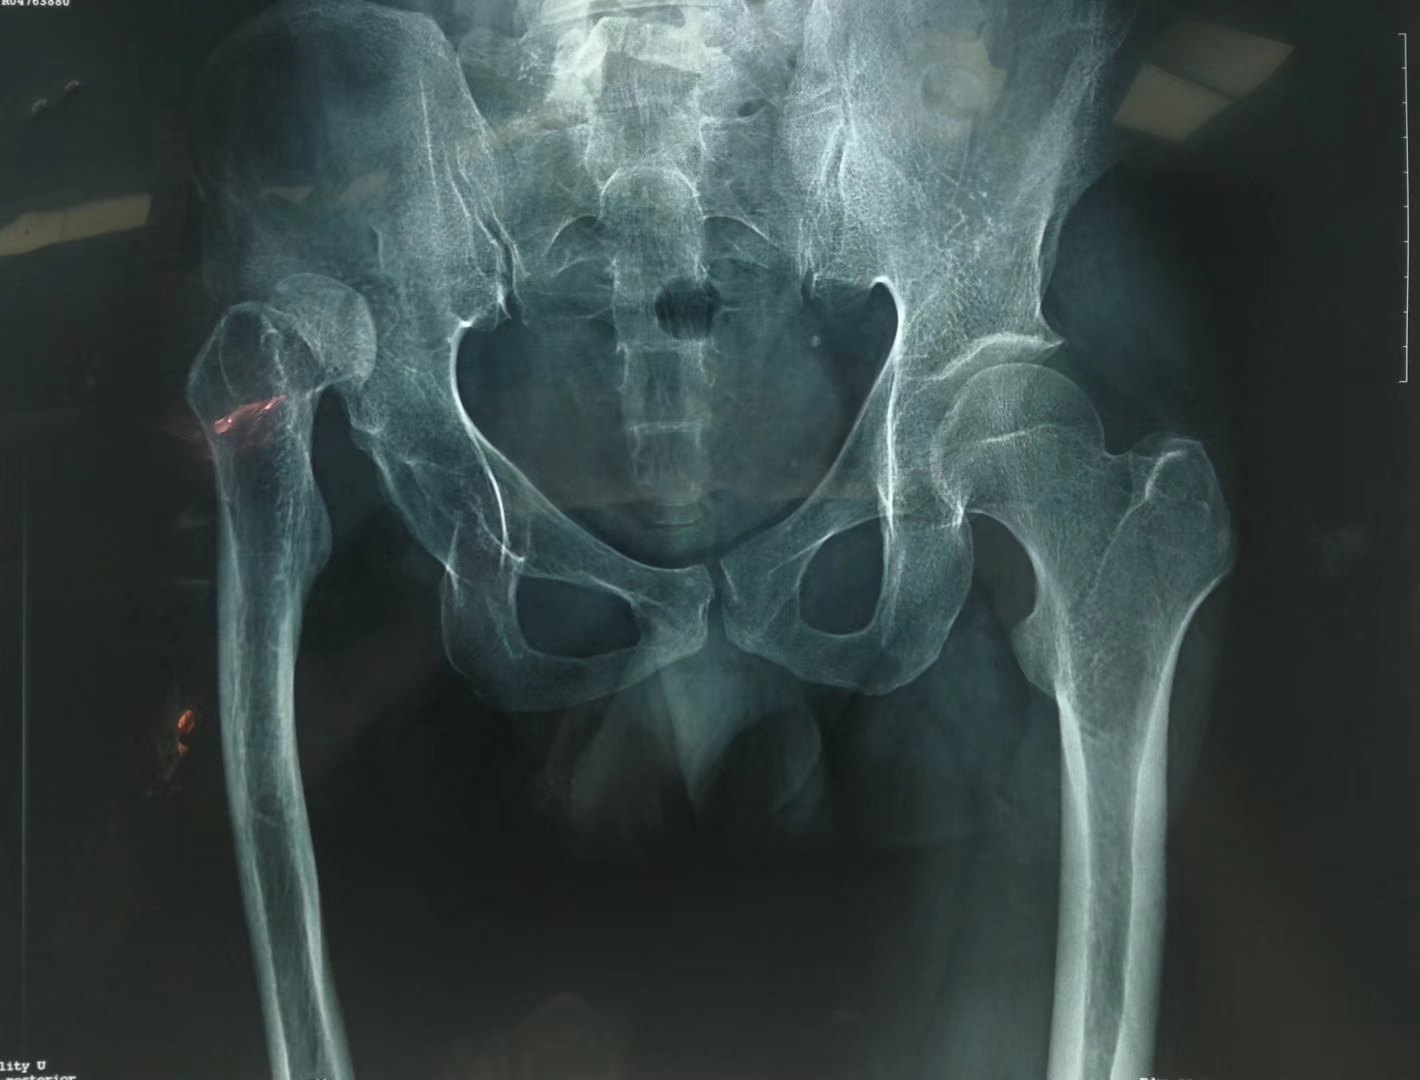

50岁髋臼发育不良继发骨性关节炎患者人工全髋关节置换手术一例

髋臼发育不良半年,x线片显示,右侧髋臼顶平缓,股骨头-髋臼接触充分

髋臼发育不良左髋关节脱位27岁什么情况下需要做手术康复效果怎么样

先天性髋臼发育不良ddh全髋关节置换术

髋关节发育不良Ⅳ型高脱位截骨关节置换手术